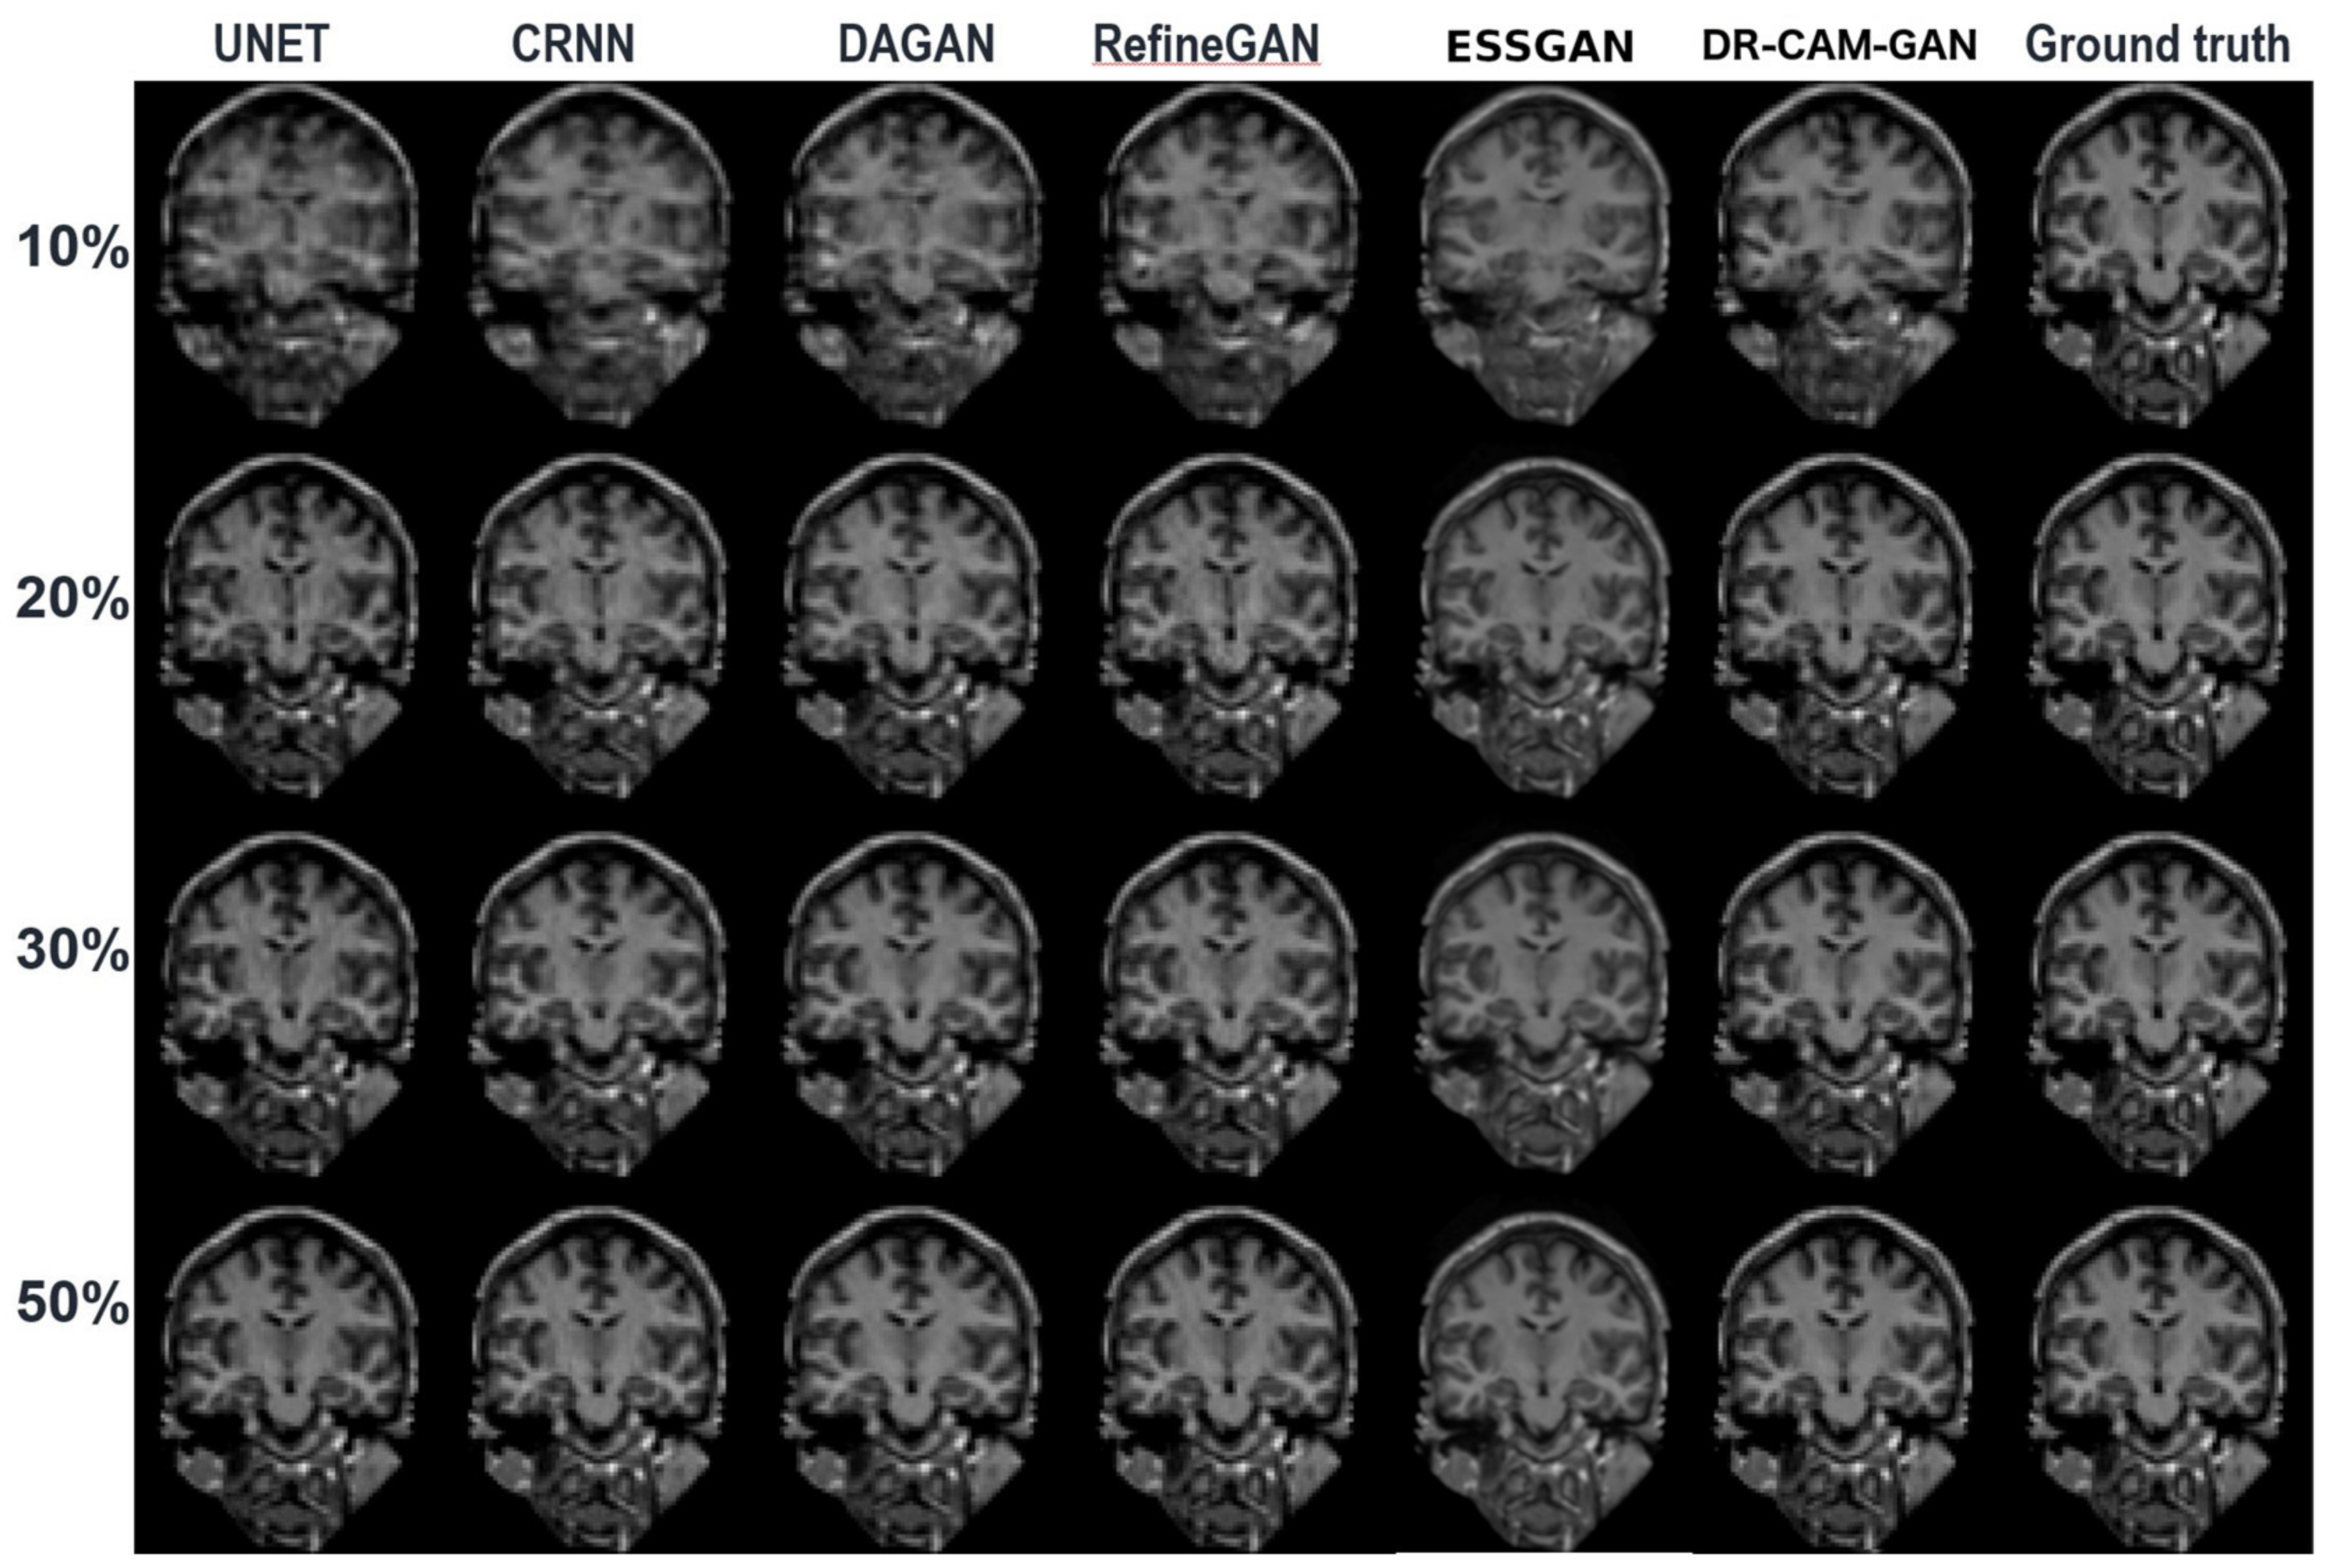

| Sampling | Model | SSIM | MSE () | PSNR (dB) |

|---|---|---|---|---|

| 10% | U-net | 0.781 | 4.75 | 28.34 |

| CRNN | 0.853 | 3.63 | 29.53 | |

| DAGAN | 0.903 | 3.29 | 30.59 | |

| RefineGAN | 0.906 | 3.22 | 30.97 | |

| ESSGAN | 0.933 | 1.96 | 31.83 | |

| DR-CAM-GAN | 0.921 | 2.76 | 31.76 | |

| 20% | U-net | 0.838 | 3.04 | 31.75 |

| CRNN | 0.887 | 1.25 | 33.16 | |

| DAGAN | 0.915 | 1.09 | 34.32 | |

| RefineGAN | 0.944 | 0.85 | 36.50 | |

| ESSGAN | 0.965 | 0.41 | 37.86 | |

| DR-CAM-GAN | 0.954 | 0.48 | 37.79 | |

| 30% | U-net | 0.857 | 1.96 | 33.54 |

| CRNN | 0.900 | 0.79 | 35.67 | |

| DAGAN | 0.944 | 0.81 | 36.69 | |

| RefineGAN | 0.951 | 0.77 | 36.95 | |

| ESSGAN | 0.972 | 0.35 | 38.62 | |

| DR-CAM-GAN | 0.966 | 0.41 | 38.43 | |

| 50% | U-net | 0.921 | 1.05 | 36.28 |

| CRNN | 0.942 | 0.50 | 38.93 | |

| DAGAN | 0.967 | 0.53 | 39.18 | |

| RefineGAN | 0.972 | 0.23 | 42.05 | |

| ESSGAN | 0.988 | 0.08 | 44.12 | |

| DR-CAM-GAN | 0.985 | 0.11 | 43.90 |